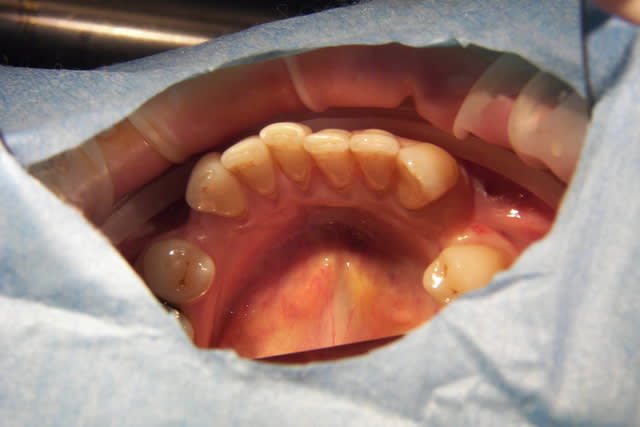

et les photos d'arcades

la patiente est inquiète car malgré la contention Inf.

"ça revient comme avant"

Au départ, il existait des Pbs. des deux cotés, inégalement répartis. maintenant le coté D. est bien, mais que dire du coté G. et du bloc Ant. qui évolue vers une Cl. II. 2, malgré une contention Inf.

tout à fait, c'est du reste ce que je vais tenter, avec un systeme à double friction: friction forte à D. car j'ai besoin d'ancrage pour friction faible à G pour expansion

j'ai besoin au départ de symétriser mes arcades avant de refaire l'occlusion G. qui sera sans doute avec une réouverture d'espace

tout cela en gardant un controle Ant.